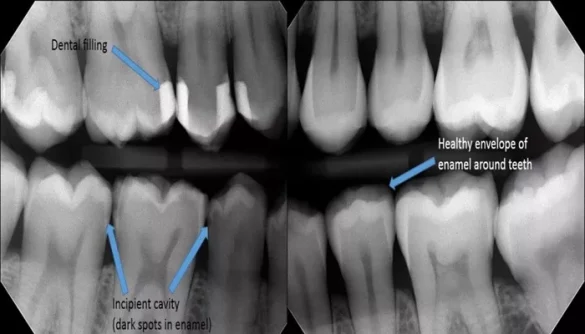

A cavity, also known as dental caries, occurs when the enamel of the tooth is damaged by acids produced by bacteria in the mouth. These bacteria feed on sugars and starches from food, producing acids that slowly wear down the enamel. If left untreated, a cavity can grow larger, causing pain, infection, and eventually tooth loss.

The most common symptom of a cavity is tooth pain, but not everyone with a cavity will experience pain right away. Early-stage cavities may not cause noticeable pain or discomfort, but they can still lead to further damage if not treated. As the cavity progresses, you may notice:

Tooth sensitivity when eating hot, cold, or sweet foods

Visible holes or pits in the teeth

Pain while chewing or biting

Persistent or sharp toothache